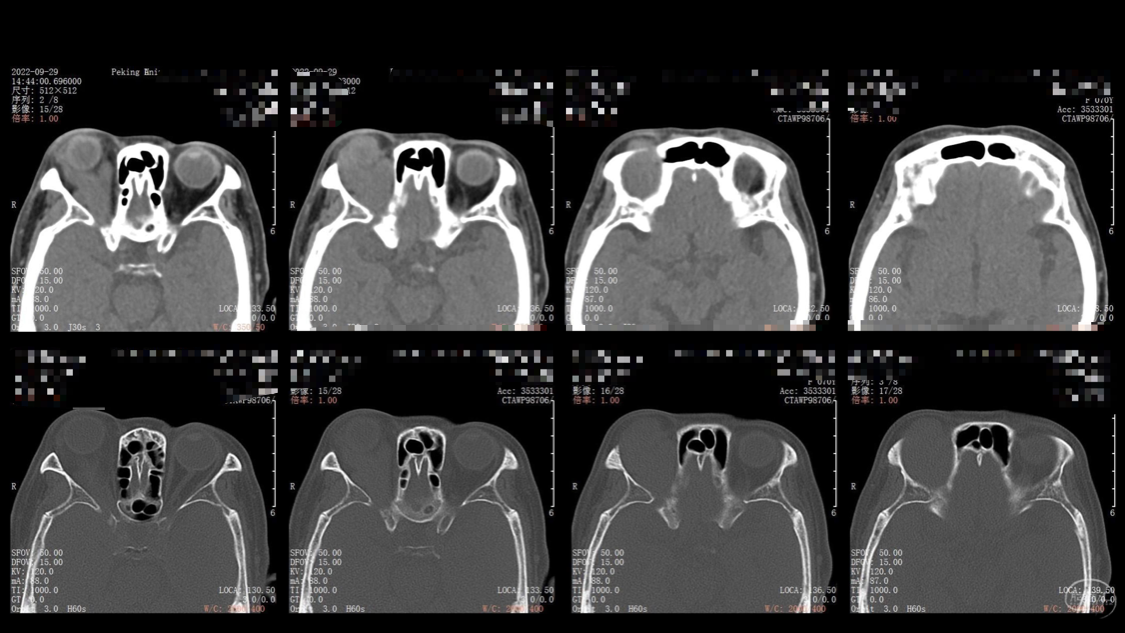

陈保东教授手术作品-右眶内及海绵窦旁孤立性纤维瘤